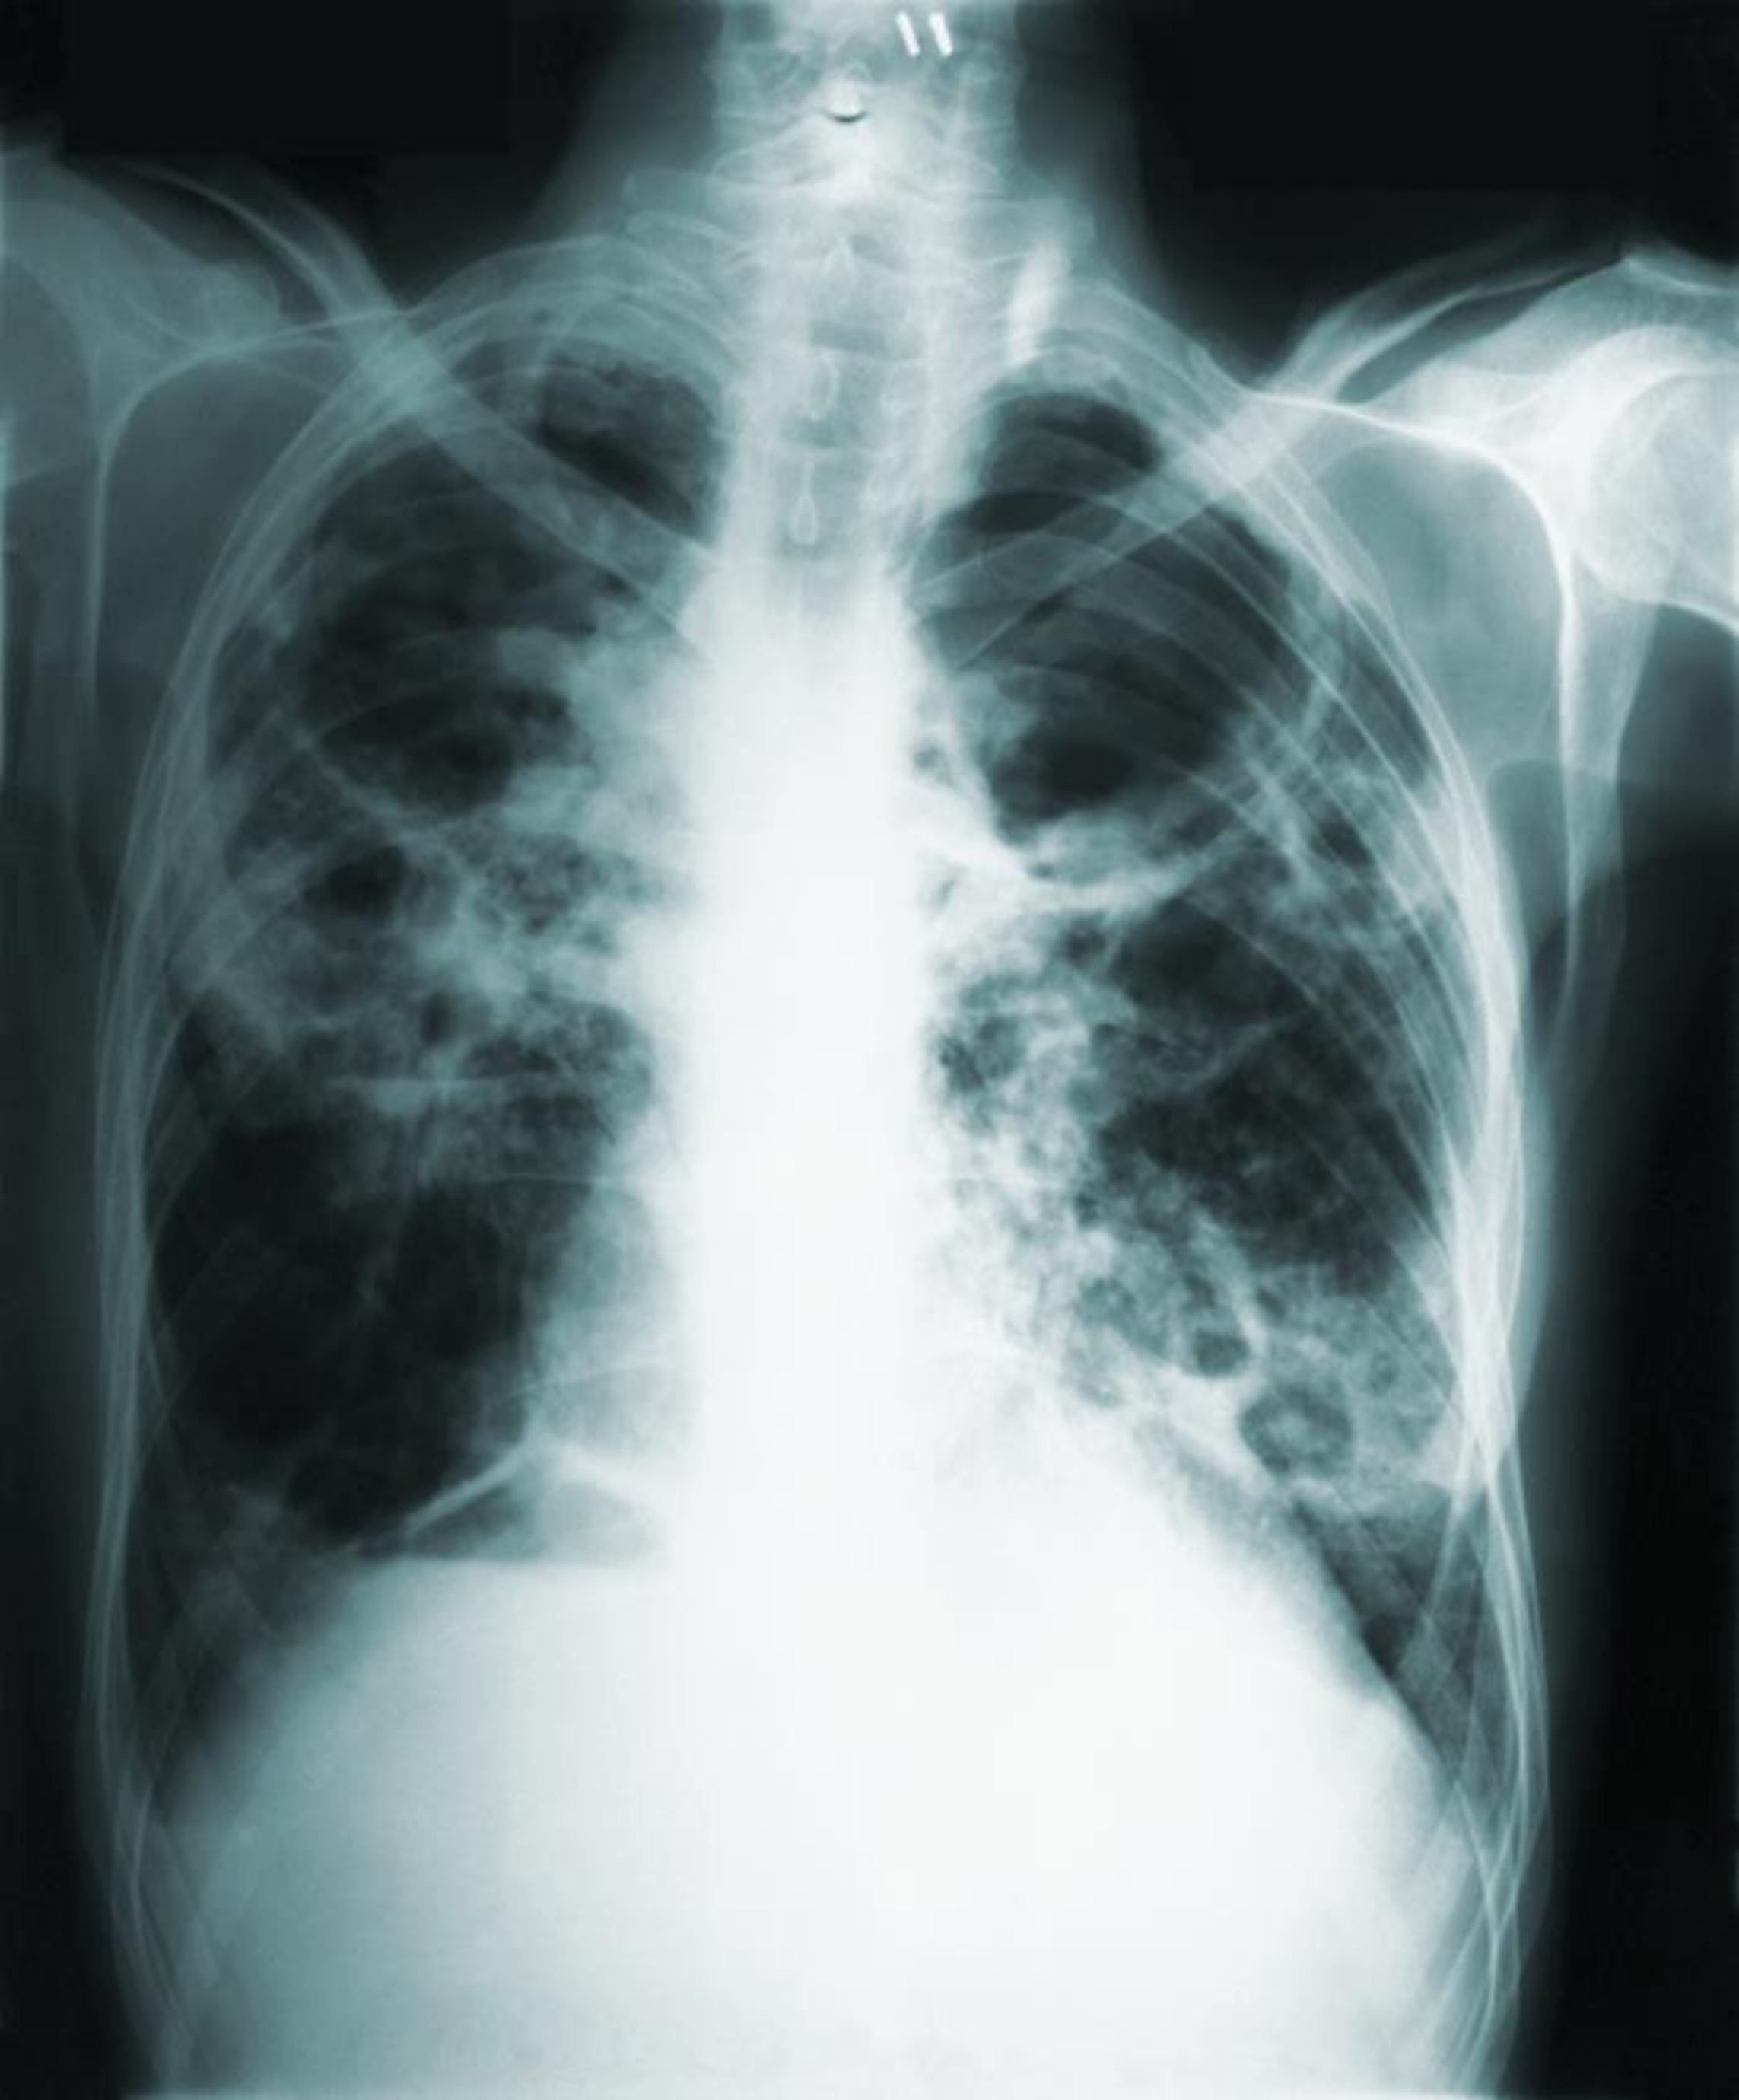

This report describes an infant death following a case of undiagnosed tuberculosis during pregnancy.